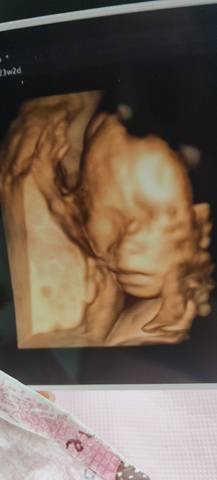

这嘴巴接了我大嘴,各位孕妈妈们你们觉得我的是女宝还是男宝